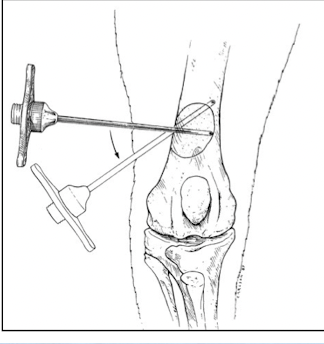

Q

what to use for core biopsy of OSA

A

Jamshidi needle

92% for dx neoplasia

82% accurate- tumor type